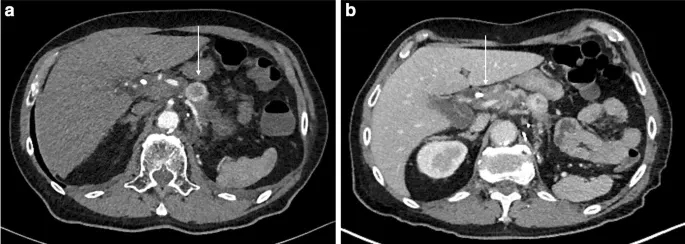

在进行肿瘤分期时,腹部超声、计算机断层扫描(CT)和胸部x线显示PDAC没有远处转移。CT扫描发现胰腺多发占位性肿块(图1)。由于放射学怀疑存在门静脉和可能的腹腔干紧邻动脉浸润,PDAC被划分为边缘可切除。

图1. 胰腺的CT扫描

(图片引自发表文章)